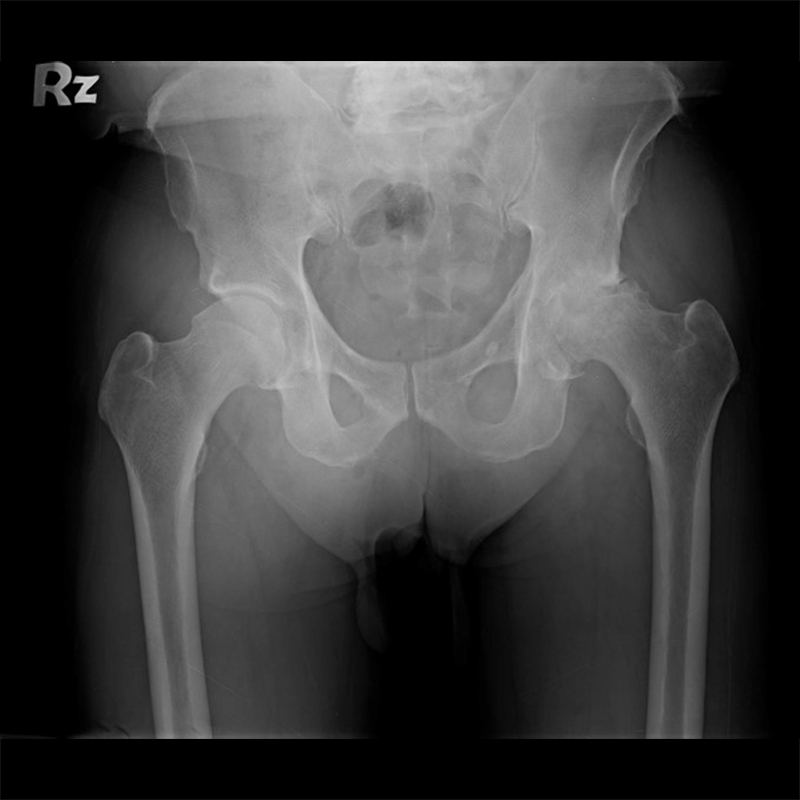

傳統髖關節置換 首頁 案例分享 髖關節手術 傳統髖關節置換 54歲蔡先生退化性關節炎 術前 術後 張女士 51歲 退化性關節炎(DDH先天發育不全 CROWE TYPE 2) 術前 術後 38歲林先生 退化性關節炎 術前 術後 72歲謝女士 退化性關節炎 術前 術後 71歲 謬女士 骨股頭壞死 術前 術後 50歲 郭先生骨股頭壞死 術前 術後 80歲 盧先生骨股頭壞死 術前 術後 林先生 37歲 術前 術後 邱女士 51歲 術前 術後 張女士 50歲 術前 術後